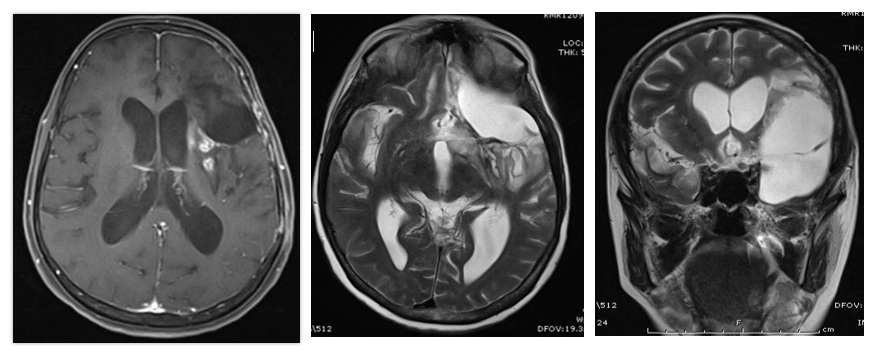

Glioblastoma Multiforme

55 M

Focal seizures since 6months

Right side weakness since 15 days

Grade 3 Astrocytoma-

45 / F

Weakness right side

Dysphasia